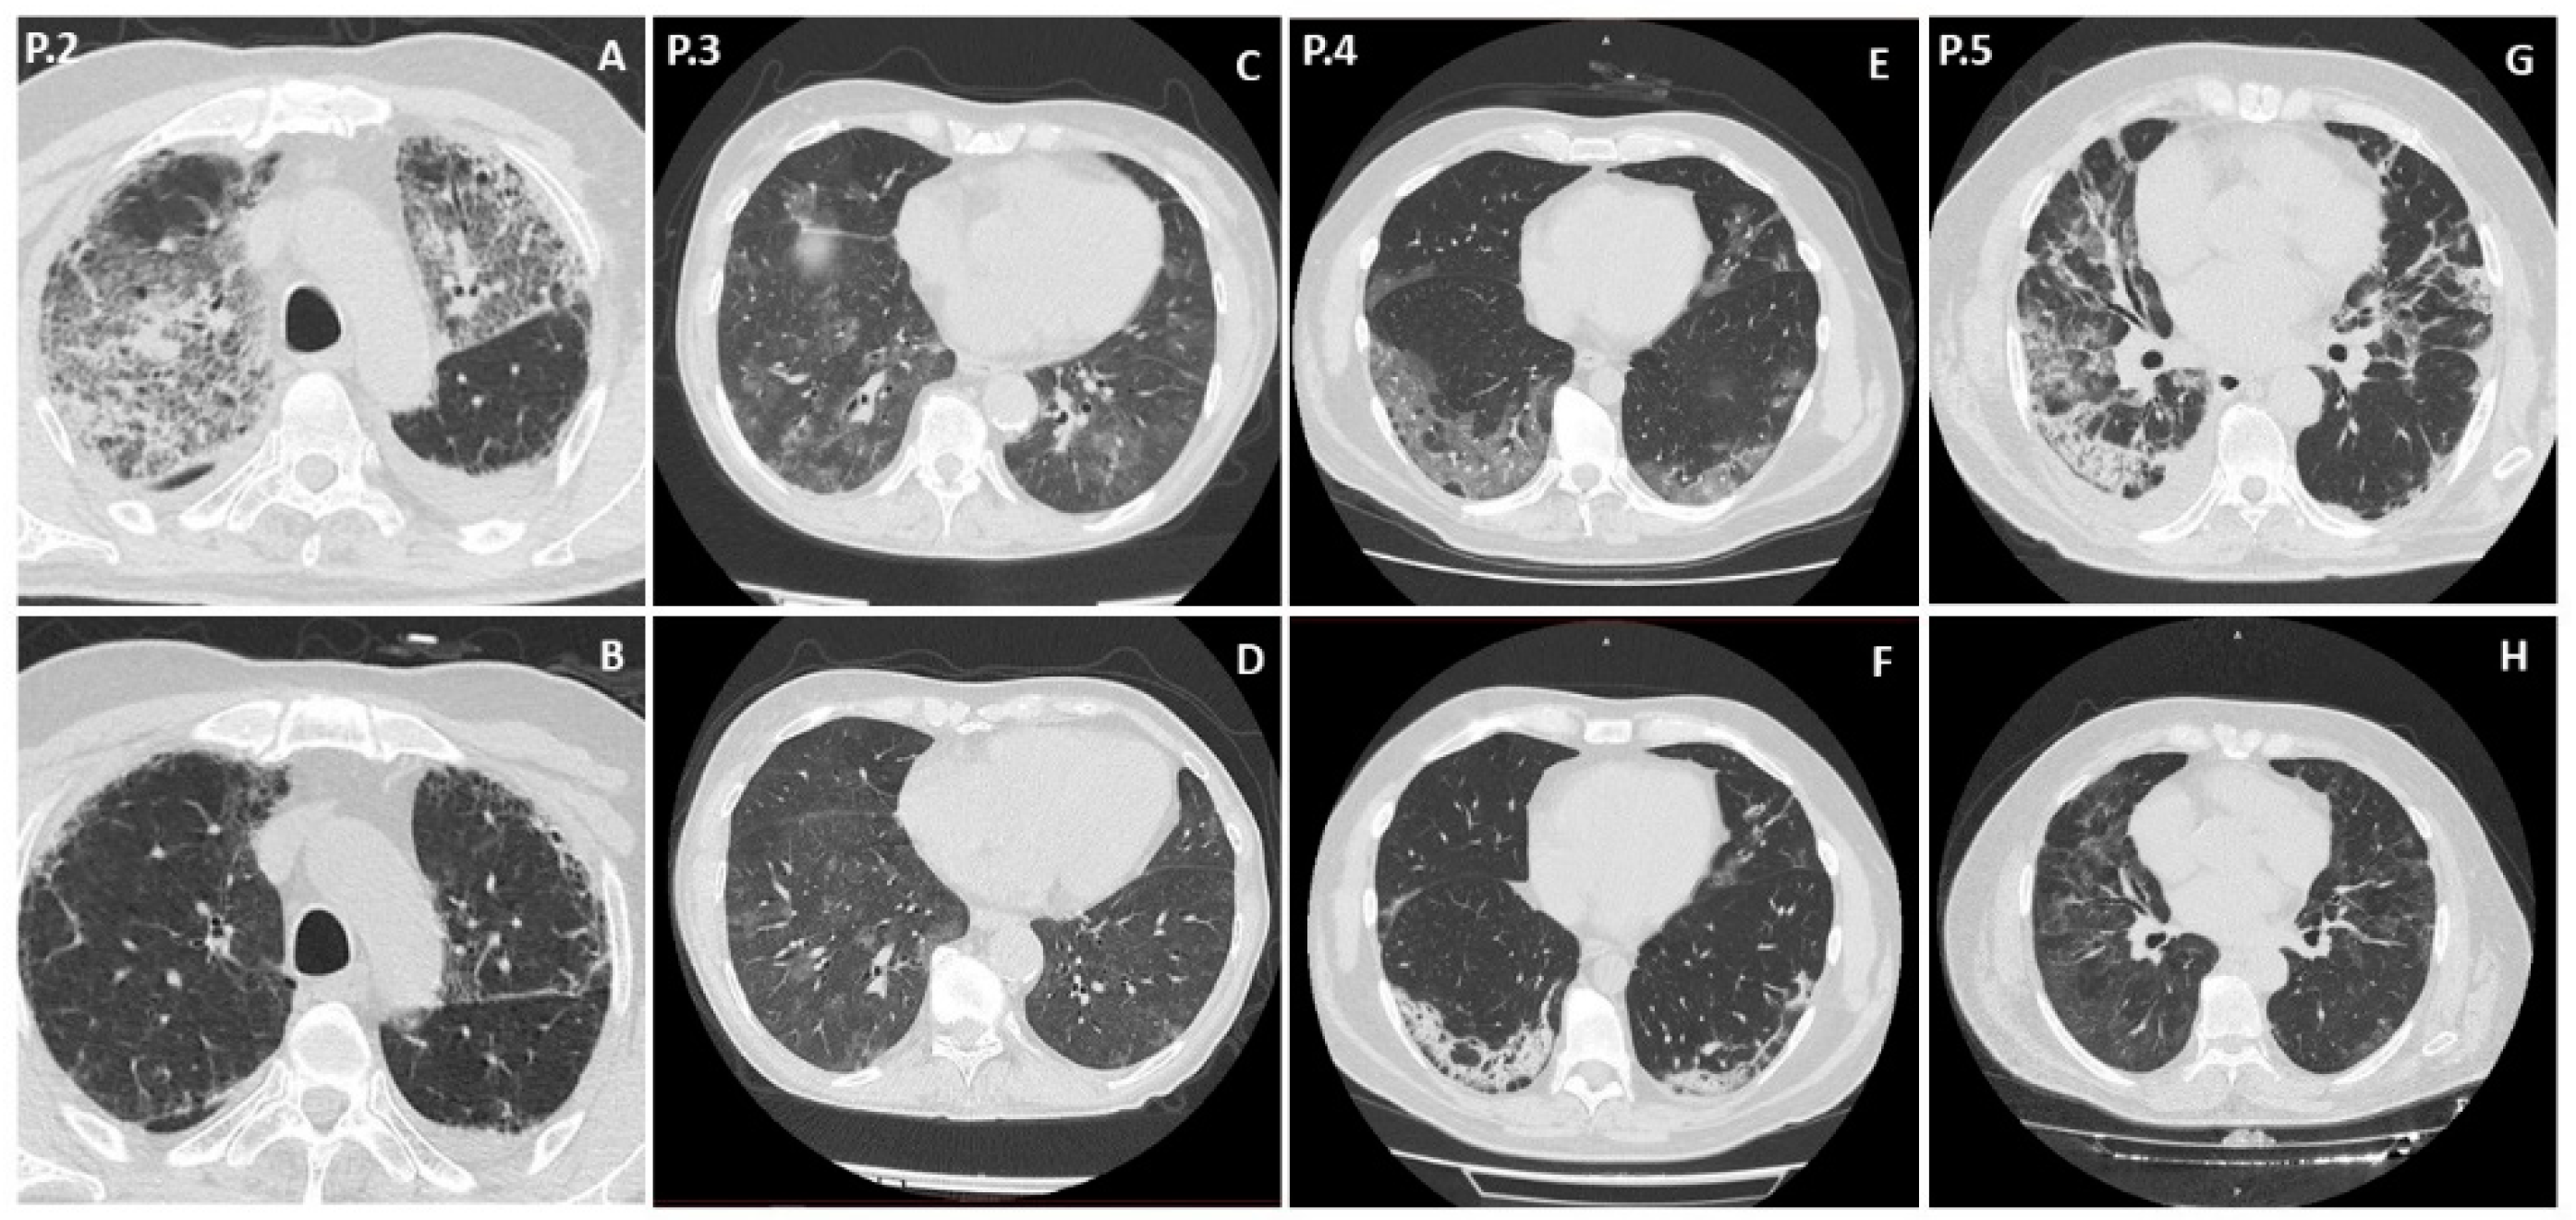

3.2. Patient 2

3.3. Patient 3

3.4. Patient 4

3.5. Patient 5